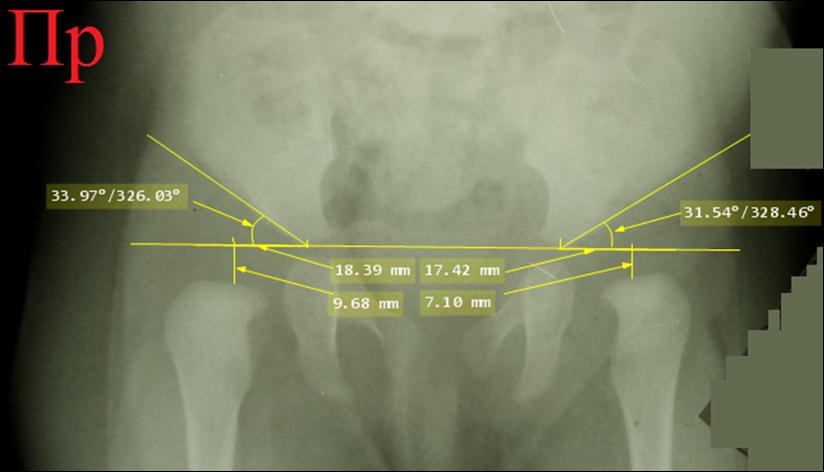

Через

3 месяца, в возрасте 10 месяцев, была сделана контрольная рентгенограмма без

ортеза, на которой все

рентгенометрические параметры значительно выходили за пределы нормы:

ацетабулярные углы превышали 30° с обеих

сторон, ядра окостенения головок бедер

не полностью покрывались крышами вертлужных впадин и большая их часть

находилась кнаружи от линий Омбредана – Перкинса. Ортезирование продолжено

ещё на 4 месяца.

Снимок

в возрасте 1 года 3 месяцев.

Рентгенометрические параметры с натяжками укладываются в норму: ацетабулярные углы превышают норму, но не так

значительно, в пределах 2-3 градусов. Угол Виберга равен не больше 2-3 градусов

с обеих сторон (не начерчен), но все же он больше нуля. Ядра окостенения головок бедер лежат не

полностью кнутри от линий Омбредана – Перкинса. Ортезирование шиной БелНИИТО прекращено.

Назначено применение шины Виленского⃰

сроком на полгода. На

контрольном снимке в возрасте 5 лет все рентгенометрические показатели были в

норме, углы Виберга с обеих сторон 25°.